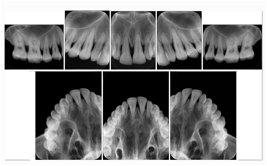

2 Occlusal Vertical Maxilla A Dental Image Layout

DL-C001A

Reference: DL-C001-U1L0

Reference: DL-C001-U2L0

2 Occlusal Vertical Mandible A Dental Image Layout

DL-C002A

Reference: DL-C002-U0L1

Reference: DL-C002A-U0L2

2 Occlusal Horizontal Maxilla A Dental Image Layout

DL-C003A

Reference: DL-C003-U1L0

Reference: DL-C003-U2L0

2 Occlusal Horizontal Mandible A Dental Image Layout

DL-C004A

Reference: DL-C004-U0L1

Reference: DL-C004-U0L2